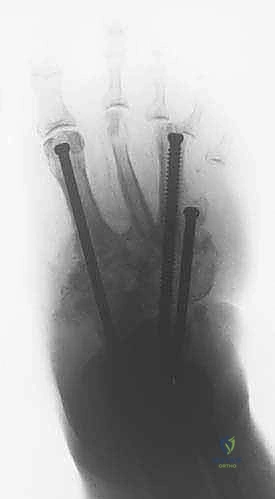

4. المرحلة الثانية: دمج المفاصل (Joint Arthrodesis)

بمجرد أن تصبح العظام في الوضع الصحيح بفضل التثبيت الخارجي، ننتقل إلى مرحلة التثبيت الدائم.

* من خلال شقوق جراحية صغيرة جداً (Minimally Invasive)، يقوم الدكتور هطيف بإزالة الغضاريف التالفة من المفاصل المستهدفة (غالباً مفاصل منتصف القدم والكاحل).

* يتم استخدام تقنيات متقدمة لتحفيز العظام على الاندماج (مثل استخدام طعوم عظمية أو بروتينات محفزة لنمو العظم).

* يتم ضغط العظام معاً باستخدام جهاز التثبيت الخارجي نفسه لضمان التحامها كعظمة واحدة صلبة.